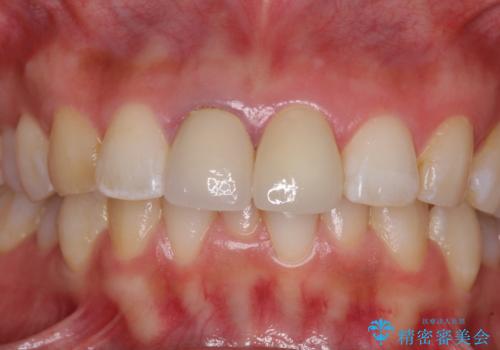

目立つ前歯の詰め物 オーダーメイドのセラミッククラウンで審美的に仕上げる

反対側同名歯にセラミッククラウンが装着されていたため、そちらのクラウンと形態や色彩を揃えるようオーダーメイドタイプのオールセラミッククラウンにて補綴することとしました。

2本同時に処置をし、2本とも明るい色合いにすることをお勧めしましたが、今回は1歯のみとしました。

左右のバランスが取れ、患者様には大変満足していただきました。